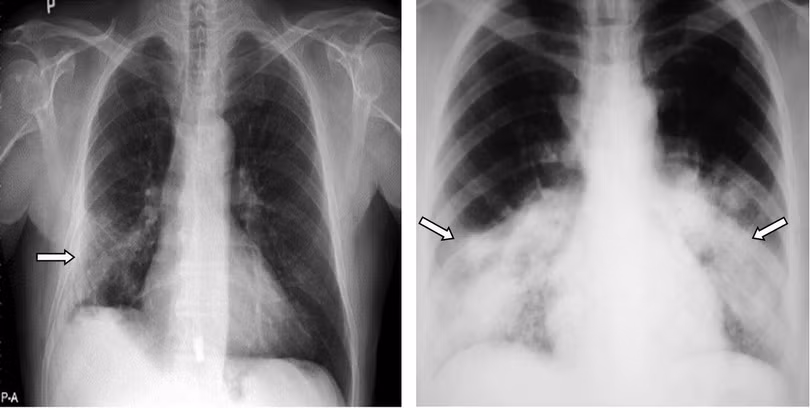

6.1. Trên hình ảnh X-quang

Các dấu hiệu điển hình:

-Nốt mờ, đám mờ, kính mờ hình tròn đa ổ.

-Đông đặc nhu mô phổi vùng ngoại vi đa ổ (nếu không phân bố ở ngoại vi thì coi là chưa xác định được).

Các dấu hiệu không điển hình, có thể do COVID-19 hoặc các nguyên nhân khác:

-Đông đặc khu trú thùy phổi.

-Tràn dịch màng phổi.

-Mờ tổ chức kẽ quanh rốn phổi.

-Dày thành phế quản, dày vách liên tiểu thùy.

-Xẹp phổi.

-Bệnh lý hạch lympho.

Vào giai đoạn sớm, hình ảnh X-quang có thể bình thường. Tổn thương thường cả ở nhu mô phổi và tổ chức kẽ. Tổn thương thường lan tỏa, thùy dưới hai bên, ở vùng ngoại vi, ít có phá hủy. Khi khỏi có thể để lại xơ phổi.

Hình ảnh kính mờ (ground glass opacity - GGO): Là tổn thương đông đặc không hoàn toàn, có tỷ trọng cao hơn nhu mô phổi xung quanh vẫn có thể thấy đường bờ các mạch máu hoặc phế quản bên trong tổn thương đó.

Hình ảnh nốt mờ: Là những hình mờ có đường kính dưới 3cm, dạng hình tròn, có thể đơn độc, có thể rải rác trong nhu mô phổi. Các nốt phổi thường có ranh giới rõ, được bao quanh bởi nhu mô phổi và không liên tục với rốn phổi hay trung thất.

Hình ảnh dày thành phế quản: Là những tổn thương thể hiện thành của phế quản dày lên, do có sự tích tụ dịch hay chất nhày xung quanh thành phế quản, trong mô kẽ.

Hình ảnh dày vách liên thùy: Liên quan đến dịch rãnh liên thùy, thâm nhiễm tế bào hoặc xơ hóa. Trong viêm phổi do virus, dày các vách liên thùy gặp trong tổn thương lan tỏa trong ARDS.

Hình ảnh phổi bị tổn thương do COVID-19 trên hình ảnh X-quang. Ảnh: BVTWQĐ 108